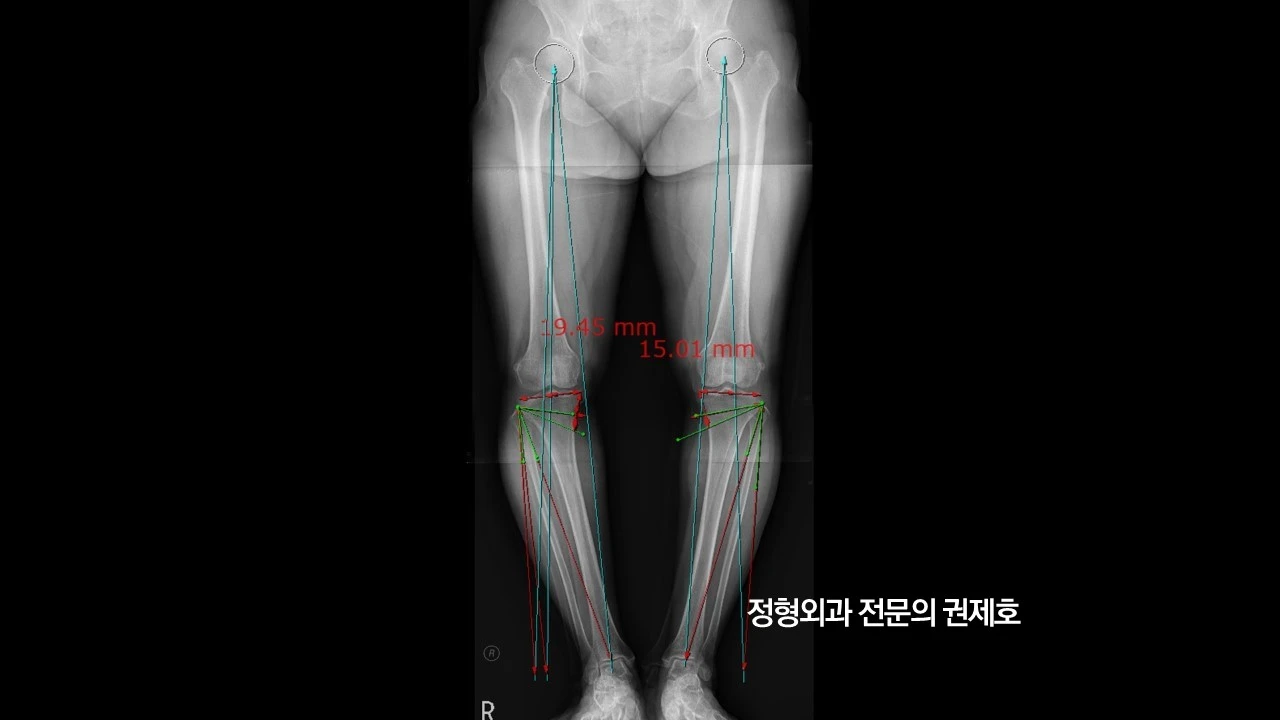

제가 가장 중요하게 여기는 하지 정렬 검사 사진입니다. 보시면 무릎이 많이 휘어 있는 것을 아실 수 있습니다. 바로 오다리입니다. 아마도 어릴 적부터 원래 오다리였다고 사료되며, 관절염으로 진단받고 관리는 하였으나 아마도 기존에 있던 휜다리가 증상 악화의 요인이 아닐까 생각하며, 비교적 젊은 나이이고, 다른 이상 소견이 있는지 확인하기 위해 MRI 검사를 진행했습니다.

무릎 절골술을 시작하기 전에 하지정렬 검사 사진을 가지고 측정을 합니다. 얼마나 교정이 필요한지를 계산하게 되고 이것을 믿고 수술을 하는 것이기게 엄청 까다롭게 정확하게 측정하게 됩니다.

2주가 되면 서있을 수 있게 되기 때문에 하지 정렬 검사를 다시 시행하게 되고, 이때 교정이 잘 되었는지를 파악하게 됩니다.

무릎절골술의 변화

무릎 절골술이 무릎과 다리에 어떤 변화를 가져다주는지 확인해보도록 하겠습니다. (좌측) 처음 내원 당시 사진이고, 우측이 무릎절골술 2주 차의 사진입니다. 어떠신가요? 다리의 모양과 축의 변화가 느껴지시나요?

이게 바로 무릎절골술을 통해 다리의 열을 바꾸어 무릎관절염의 진행을 막으면서 동시에 무릎의 통증을 잡아주는 관절염 초기, 중기에 사용되는 수술 방법입니다.